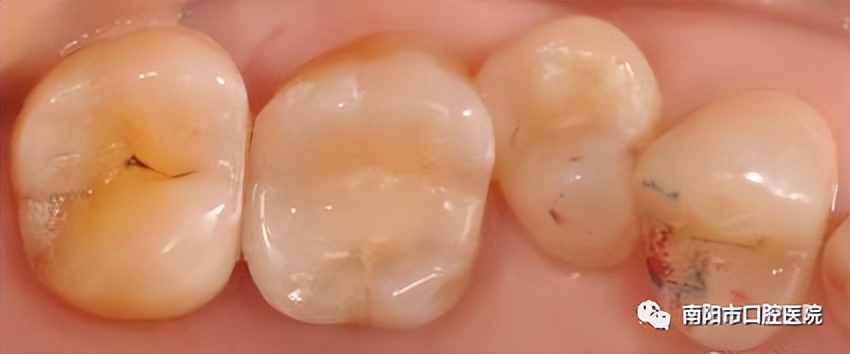

根管治疗后全瓷冠修复